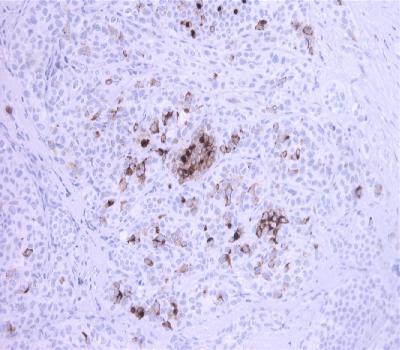

Figure-1: Breast Cancer section has been stained using Mammaglobin antibody (Clone: BS17).